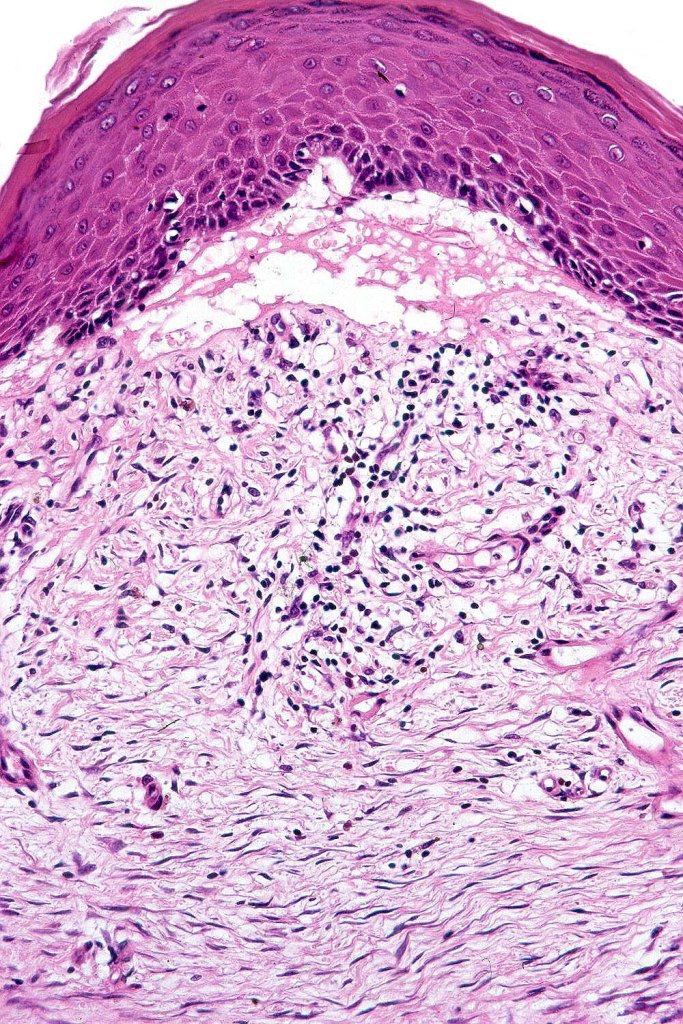

Histological features

•Generally, tumors are well differentiated although they can later develop a more poorly differentiated morphology

•Keratoses may represent a precursor & sometimes histological distinction between very marked epidermal hyperplasia (pseudoepitheliomatous) and early SCC can be problematical (personal observation)